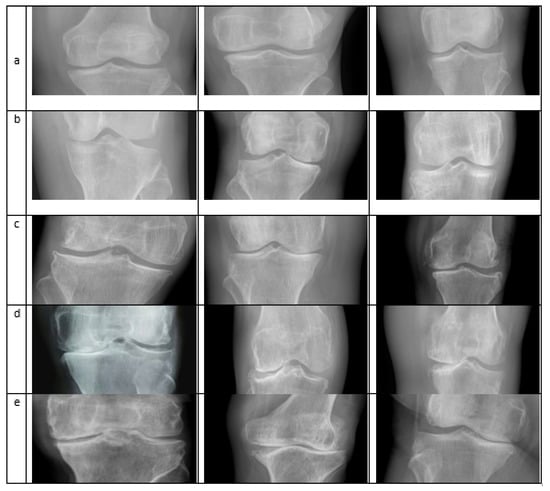

The Knee Osteoarthritis Severity Grading dataset, known as the Mendeley dataset IV [47], is used. The experiment was performed on a system Core-i7-7700K 4-core 4.2 GHz with 32 GB RAM (Intel Corporation, Santa Clara, CA, USA) and with NVIDIA Titan V providing 12 GB memory (Nvidia Corporation, Santa Clara, CA, USA). The dataset was collected from different hospitals. X-ray images were taken from the machine, PROTECT PRS 500EX-ray. All the images were in grayscale form and were labeled manually according to KL’s grading system. A total of 500 images were used to train the classifier, of which 100 images showed healthy knees without KOA. For each Grade, according to KL, 100 images were used for the training. A five-fold validation was used, such as (50,50), (25,75), (30,70), (40,60), (20,80); here, an individual set represents the training and testing data respectively for each Grade and the last set is for the healthy class. The algorithm produces an accuracy of 98% for five-fold validation using the KNN algorithm and the combined feature vector of CNN and HOG and SVM with CNN feature vector gives an accuracy of 97.6%. The sample images from different classes are shown in Figure 4.

Figure 4.

Different images taken from the Dataset: row (a) Normal Images; (b) Doubtful Images; (c) Mild; (d) Moderate; (e) Severe [48].